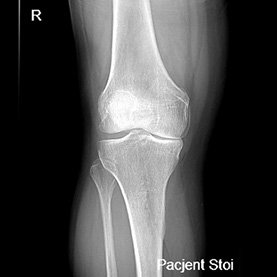

Endoproteza stawu kolanowego

Endoprotezoplastyka stawu kolanowego to skuteczna metoda leczenia zaawansowanej choroby zwyrodnieniowej kolana. Zabieg polega na chirurgicznym usunięciu uszkodzonych powierzchni stawowych i ich zastąpieniu nowoczesnym implantem – całkowitym lub częściowym – który przywraca funkcję stawu, poprawia jego stabilność i eliminuje ból. Leczenie to jest przeznaczone dla pacjentów z silnymi dolegliwościami bólowymi, ograniczeniem ruchomości, sztywnością kolana oraz brakiem efektów leczenia zachowawczego.